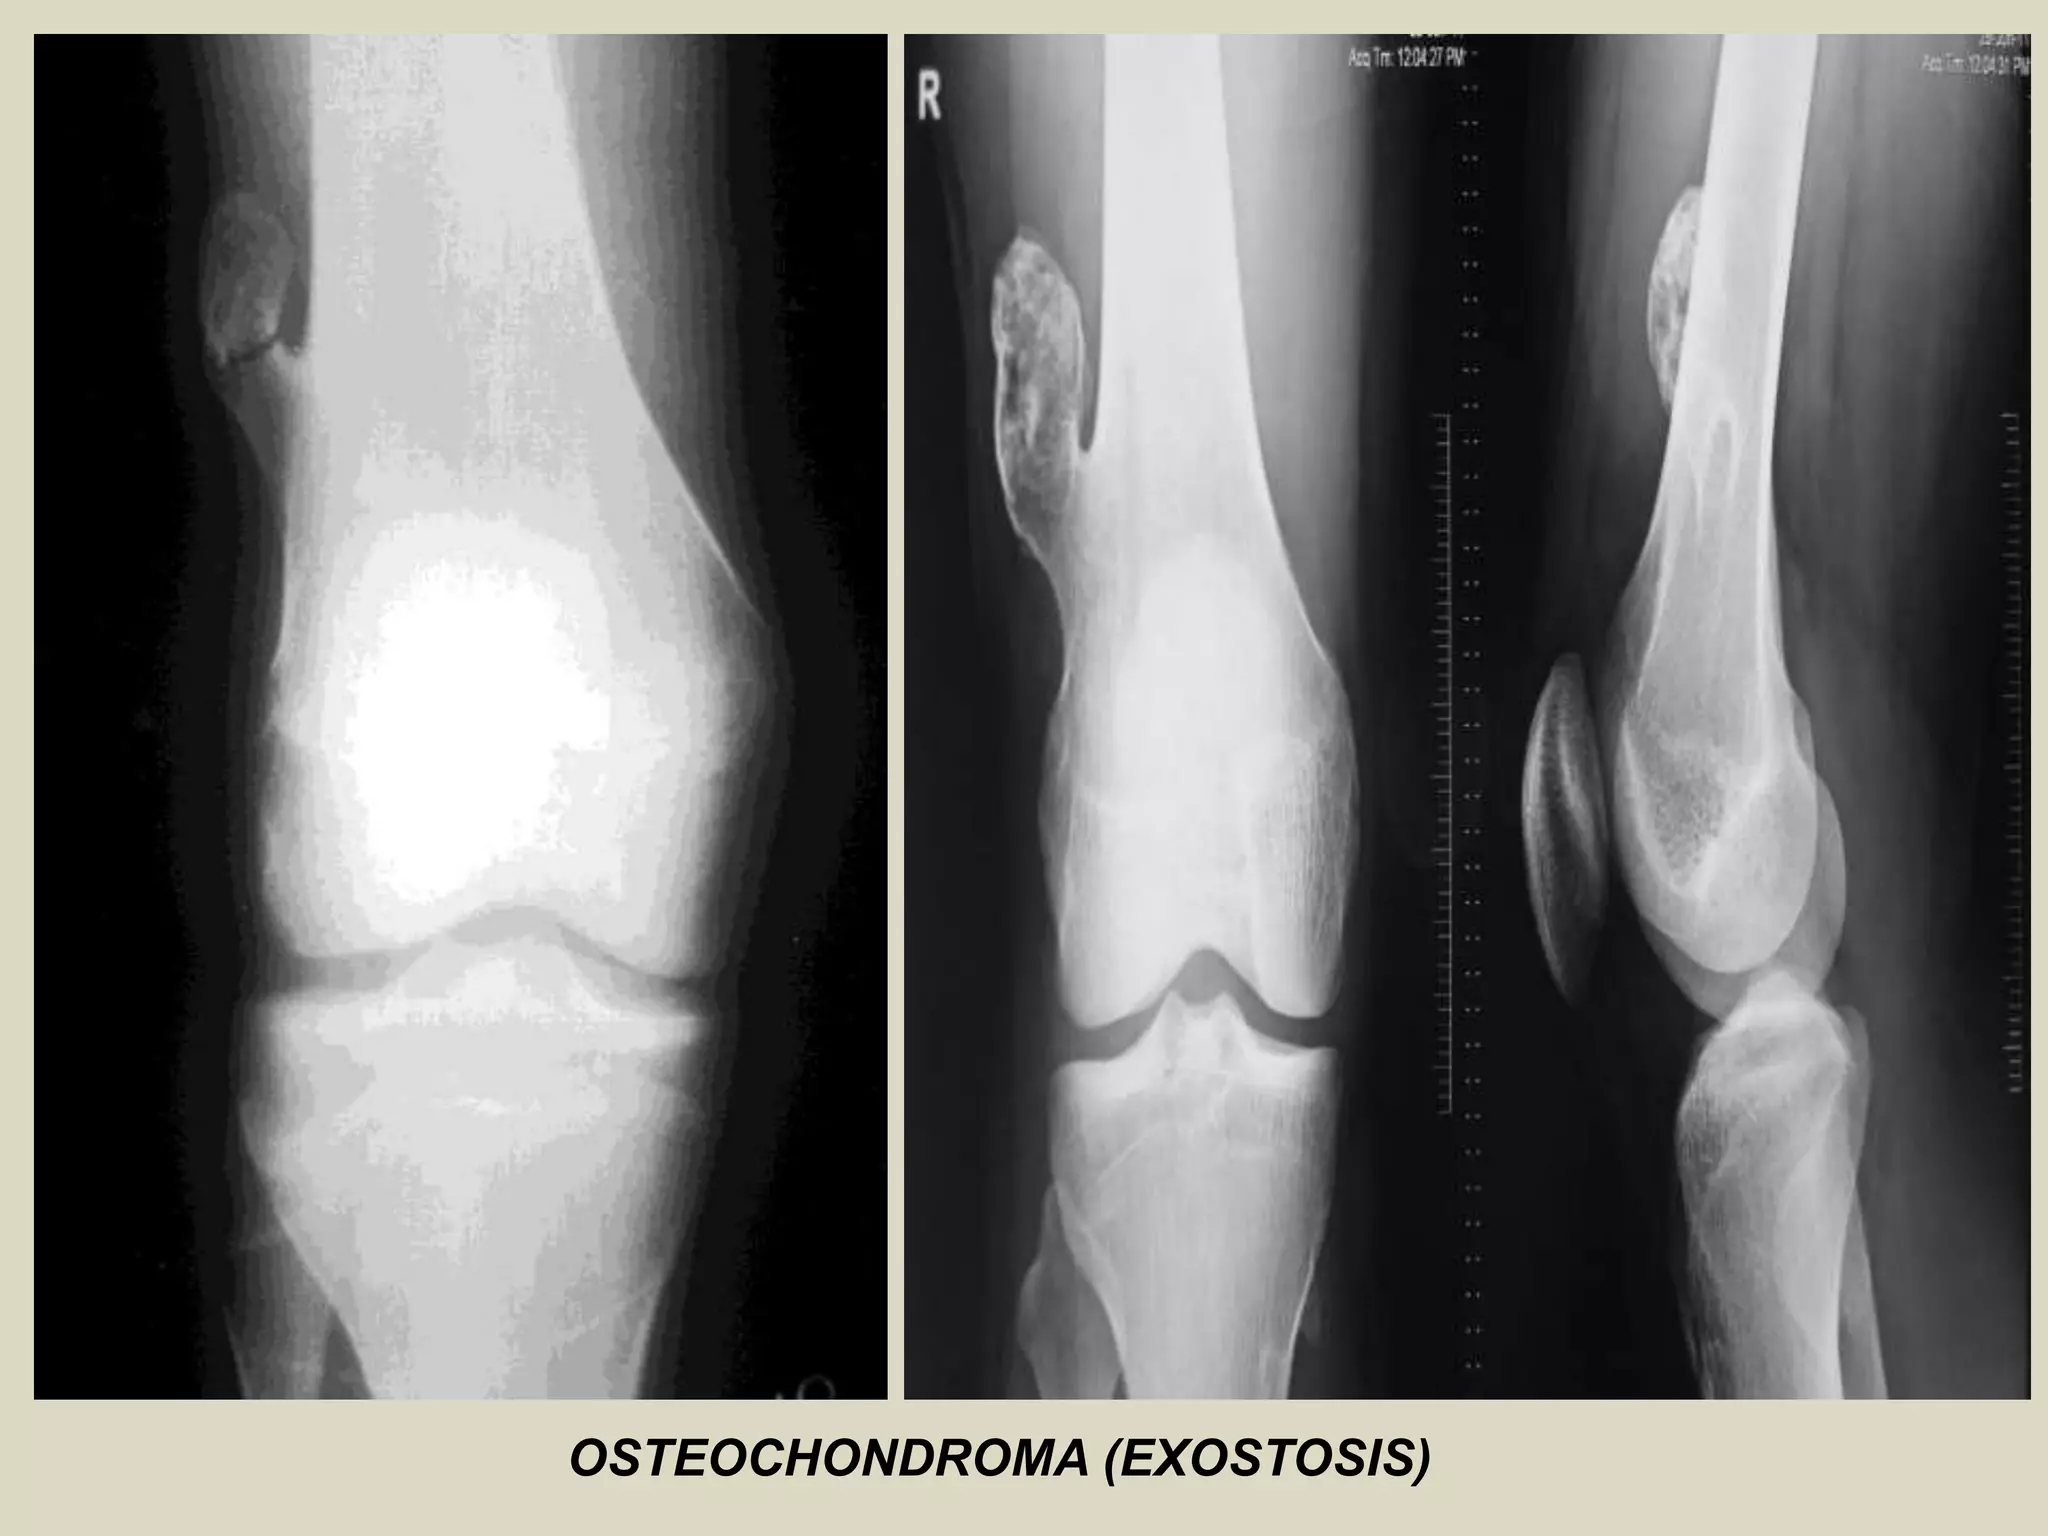

OSTEOCHONDROMA (EXOSTOSIS)

Definition: Cartilage capped bony projection arising on the external surface of bone containing

a marrow cavity that is continuous with that of the underlying bone.

Epidemiology:

-Most common bone tumor.

-Osteochondroma may be solitary or multiple, the latter occurring in the setting of hereditary multiple

exostoses.

-Solitary lesions account for 80% of cases, and most affected patients are diagnosed in their second decade .

- Male preponderance with a male to female ratio 1.5-2:1.

- Hereditary multiple exostoses (HME) is an autosomal dominant genetic disorder, and has prevalence

of 1 per 50 000 in the general population making it one of the more common inherited skeletal disease.

- Patients with HME come to medical attention at the younger age , usually during first decade, because

they cause severe skeletal deformities and are frequently polyostic.

Sites of involvement:

- Generally arise in bones performed by cartilage.

- Most common site of involvement is the metaphyseal region of distal femur, upper humerus, upper tibia

and fibula.

Clinical findings:

- Many, if not most lesions, are asymptomatic and found incidentally. In symptomatic cases, the symptoms

are often related to the size and location of the lesion.

- Most common presentation is that of a hard of long-standing duration.

Imaging:

- Bulbous lesions on X rays, and they a narrow or broad (sessile) osseous radiosense stalk, which is attached

to the underlying bone.

- The characteristic feature is a projection of the cortex in continuity with the underlying bone.

- Excessive cartilage type flocculent calcification should raise the suspicion of malignant transformation.

- CT scan or MRI images typically show continuity of the marrow space into the lesion. A thick cartilaginous

cap rises suspicion of malignant transformation.

(A and B) In the knees, radiographs showing multiple

lesions in the proximal regions of the tibias and fibulas.